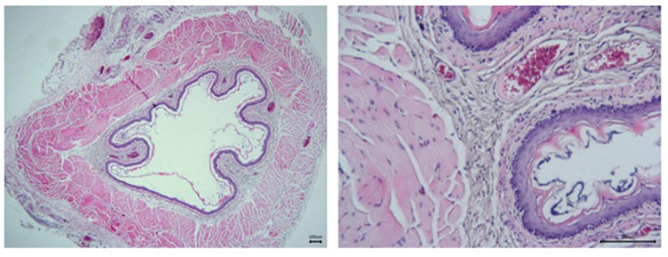

大鼠食管组织HE染色:模型组

- 组织学检查可观察食管黏膜的病理变化,如炎症浸润、细胞增生等。